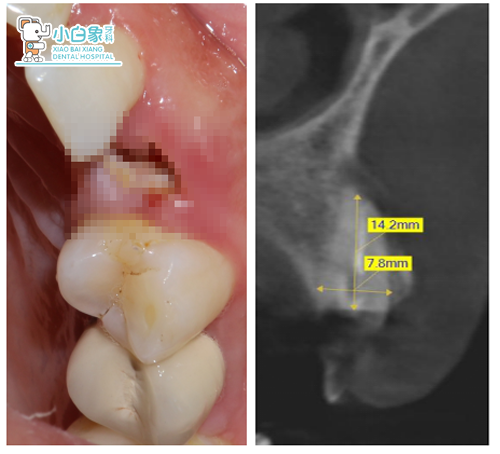

检查:颌面部未见异常,口内查:23残根齐龈,牙龈无红肿。

口内像+X线片

治疗过程:23必兰局麻下切开翻瓣,拔除残根,根尖区骨缺损,根尖大量肉芽组织,彻底去除后24根面部分暴露,预备种植窝后植入ITI3.3*12mm骨水平种植体一枚,上愈合帽后填塞Bio-oss骨粉,海奥膜覆盖,严密缝合。

残根